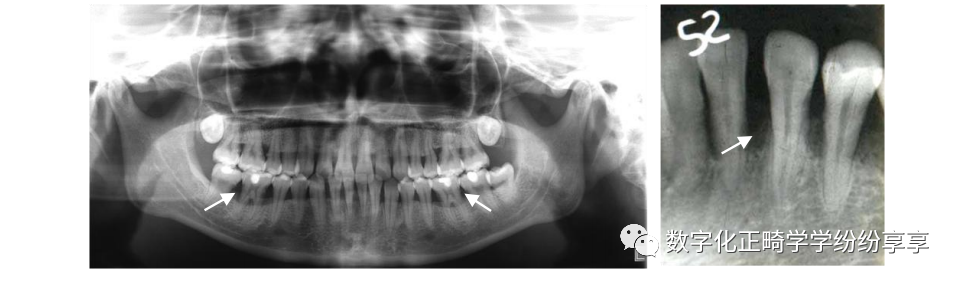

牙骨质结构不良

曲面断层片怎么看正畸【曲面断层片(全景片)】如何解读和查看:牙周?牙体?牙髓?关节?_https://www.jmylbn.com_新闻资讯_第12张

①下前牙根尖区骨质溶解破坏,类似根尖周炎;②牙骨质小体形成;③④根尖形成团状钙化影像